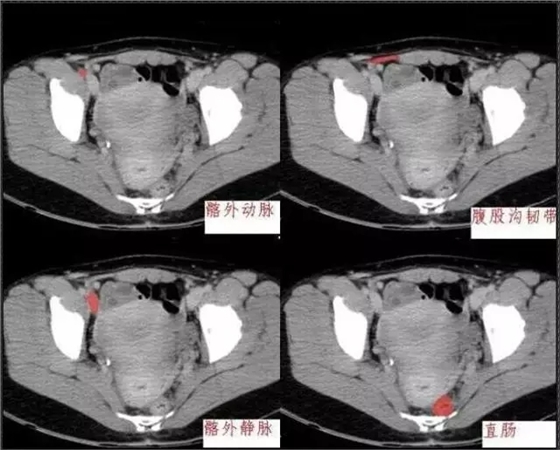

首頁(yè)口腔影像 秒懂:腹部 CT 看這篇就夠

秒懂:腹部 CT 看這篇就夠